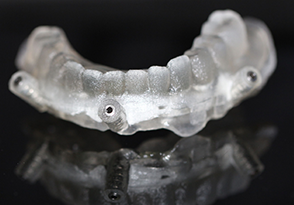

7.导板设计(分层导板-美尚专利)

8.Polyjet Technology...

9.导板打印完成(专利产品)

10.导板打印完成(专利产品)

11.分层导板有助于口内就位